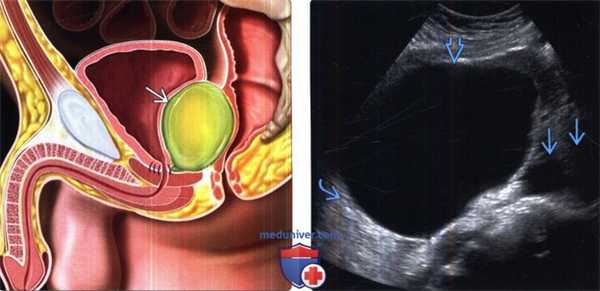

(Слева) На рисунке показана анатомическая ситуация после радикальной простатэктомии с расширенной лимфодиссекцией. Лимфоцеле, образовавшееся в малом тазу, оказывает давление на мочевой пузырь и прямую кишку.

(Справа) УЗИ, трансвагинальный датчик, поперечная плоскость: у пациентки после гистерэктомии с лимфодиссекцией выявлена крупная анэхогенная киста, прилегающая к подвздошным сосудам, что соответствует картине послеоперационного лимфоцеле. Обратите внимание на тонкую стенку и артефакт дистального усиления.